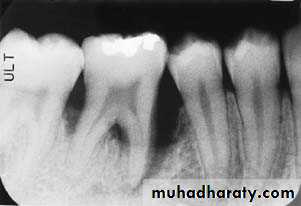

Calculus

Subgingival calculus that appears as irregular radiopaque projections in the maxillary anterior region.

Calculus that appears as sharp, pointed radiopacities along the surfaces of mandibular anterior teeth.